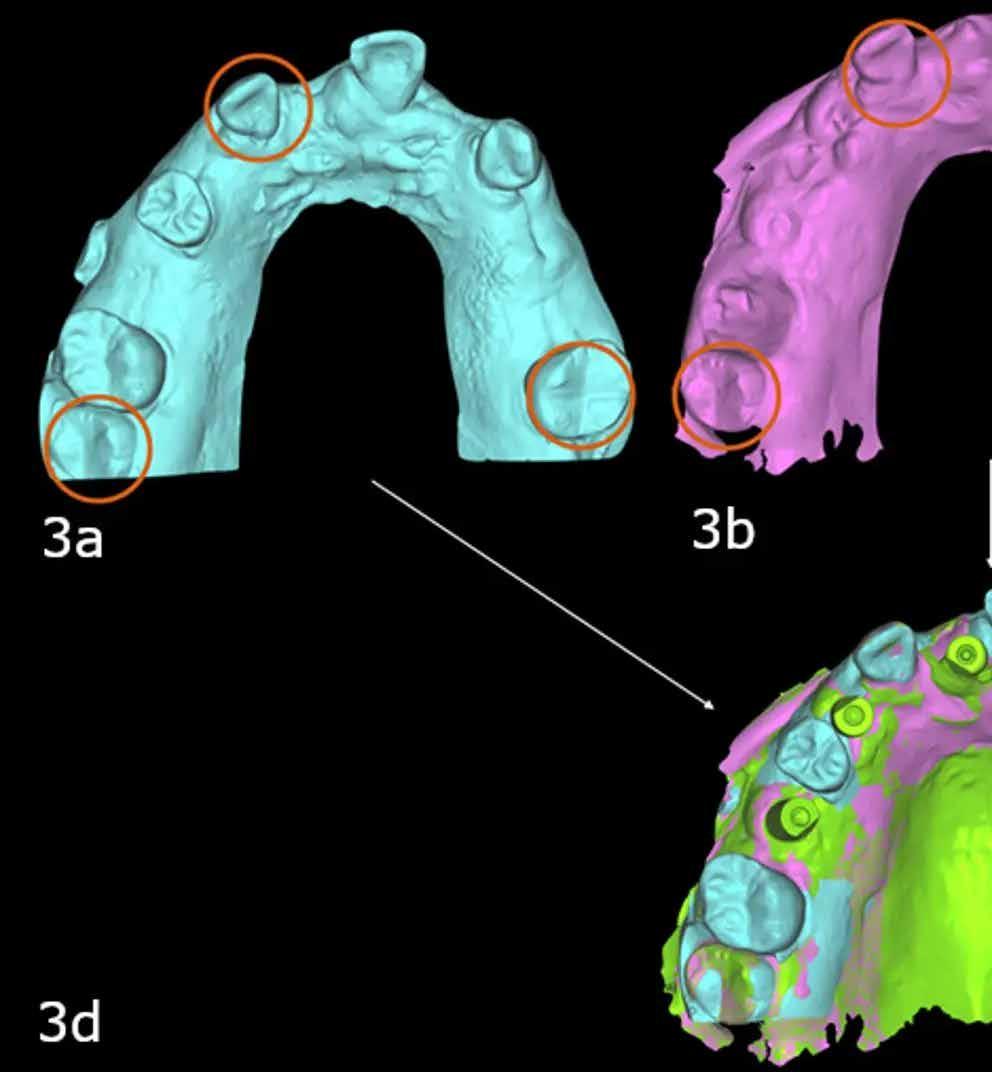

Részlegesen fogazott eset

A digitális folyamat a digitális wax-up készítéssel kezdődik jóval a műtét napja előtt. A megfelelő tervezés minden esetben létfontosságú a kezelés sikeréhez. A fogak elhelyezkedésének véglegesítése után elkészülhet a sebészeti terv az implantátum beültetéséhez. A virtuális wax-upot elmentjük, és a műtét napján szükség lesz rá a digitális átalakításhoz (2. a és b ábra). A műtét napján a digitális átalakítás fontos tényezője a műtét (foghúzás és implantátumbehelyezés) és az intraorális felvételek sorrendje. A digitális technológia egyik előnye, hogy a közös pontokat össze lehet vonni az egyik felvételről a másikra. A konverzió alapja a műtét napján készült implantátumszkennelés és a műtét előtti szkennelés megfelelő összevonása, így az eredeti wax-up helyének meghatározása az új implantátumszkennelésen. Ha nincsenek referenciapontok az eredeti szkennelés és az implantátumszkennelés között, a két szkennelés összevonása nehézségekbe ütközik, és az új implantátumszkennelés elveszik a 3D térben, és nem lehet viszszautalni rá. Ezért fontos, hogy a műtét előtt megfelelő tervvel meghatározzuk a referenciapontokat. Azokban az esetekben, amikor a páciens még fogazott vagy részlegesen fogazott, a szelektív foghúzás és bizonyos fogak megtartása referenciaként egyszerű módja annak, hogy lehetővé váljon a szkennelések pontos összevonása a műtét előtti szkenneléssel. A szkennelések egyesítése után (3. a–d ábra) az eredeti waxup az új implantátum szkenneléséhez viszonyítható. A fogászati szoftver (DentalCAD, exocad) segítségével megtervezhető az átalakító protézis a wax-upban lévő fogak és az

3. a–d ábra: A szelektív extrakció három fogat hagyott közös pontként a műtét előtti (a), az ideiglenes (b) és az implantátum intraorális felvételek (c) között, hogy a szoftver egyesíteni tudja a fájlokat, és az implantátum felvételét ugyanabban a 3D térben helyezze el, mint a műtét előtti felvételt, amelyen a wax-up volt.

implantátumok összekapcsolásával. Ez a folyamat általában körülbelül 30 percet vesz igénybe, mivel a tervezési idő nagy részét a wax-up műtét előtti megtervezése teszi ki (4. a–d ábra). A digitális átalakítás után a protézist 3D nyomtatással kinyomtatják, feldolgozzák és behelyezik az azonnal behelyezett implantátumokra (5. és 6. ábra).

4. a–d ábra: A műtét előtti maxilláris intraorális felvétel a digitális wax-up (a és b) és az implantátumfelvételen (c és d) a protézisre konvertált digitális wax-up (a és b).